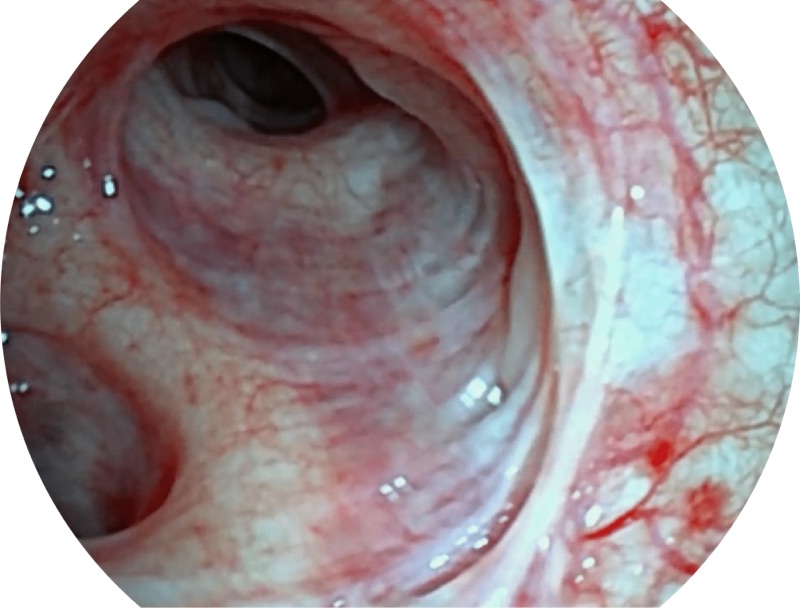

• 高清画质

帮助医生更加清晰地观察气管表面病灶

• 白光